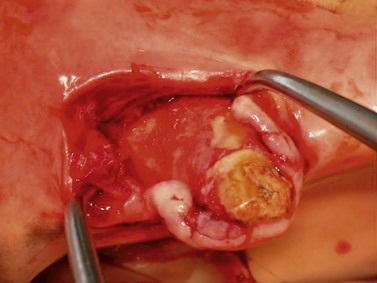

Extracting a cheek tooth using a surgical approach

Surgical removal of teeth usually involves either a retrograde (i.e., via the apex) approach or creation of a mucoperiosteal flap with a partial alveolar osteotomy to expose the reserve crown of the tooth. Retrograde removal of a tooth by repulsion became fashionable during the late 19th and early 20th centuries, when general anesthesia of the horse became possible, and the technique has changed little since this time. Complications associated with retrograde removal of a tooth by repulsion resulted in the development of an alternative surgical technique for removal, the buccotomy approach, which entails exposing the reserve crown of the tooth by removing its lateral alveolar wall through an incision into the oral cavity and then removing the tooth after dividing it into segments.